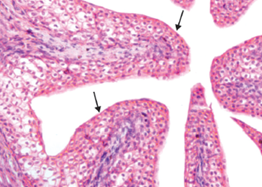

Q8. Identify the structure where the shown epithelium is located:

- Esophagus

- Ureter

- Fallopian tube

- Trachea

Answer: B